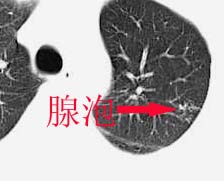

左侧中量胸腔积液伴左肺下叶肺膨胀不全、上肺外围多个小囊样腺泡样病灶。考虑化脓炎症。

以下是引用drzhang8888在2006-4-1 23:22:00的发言:[br]左侧中量胸腔积液伴左肺下叶肺膨胀不全、上肺外围多个小囊样腺泡样病灶。考虑化脓炎症。[br]心包积液没有,纵隔积液。[br]纵隔肿大淋巴结不明显。